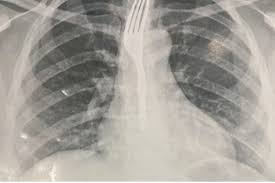

A mulher, que não teve o nome informado, foi inicialmente levada para o Hospital Geral de Guanambi (HGG), onde exames de imagem apontaram que o objeto estava alojado no esôfago em posição de risco.